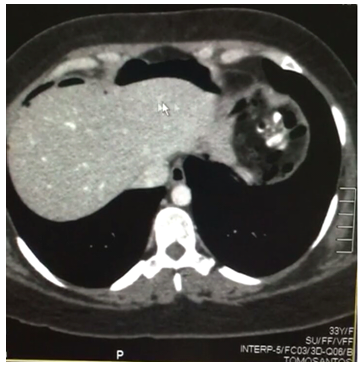

J.N.M.P., 33 years old, female, was submitted to a laparoscopic Roux-in-Y Gastric Bypass due to severe obesity (BMI 41 kg/m2) and hepatic steatosis. On the seventh postoperative day (PO), she complained of bilateral shoulder pain. There were no significant alterations on the physical examination, no fever and normal pulse. The secretion present in the drain was serous and methylene blue oral intake test was negative. Laboratory tests revealed leukocytosis of 13,000 without other changes. Abdominal CT scan with oral and intravenous contrast showed no signs of leakage, free intracavitary fluids or collections but the presence of a large volume pneumoperitoneum, not expected for a seventh postoperative day. Leading with a hypothetical fistula, consistent with the indirect CT findings, and in the absence of sepsis signs, we started a treatment with fasting, antibiotic therapy and parenteral nutrition. Three days later, there was 80 to 90% improvement of the clinical onset of shoulder pain, and reduction of leukocytosis. Eight days later, another CT showed an important reduction in the pneumoperitoneum volume, which allowed to reestablish oral intake. The patient had a good evolution. Another Tomography, fifteen days after hospital discharge, showed no pneumoperitoneum (Figures 1-4).1–3

Figure 2 TC ABDOME